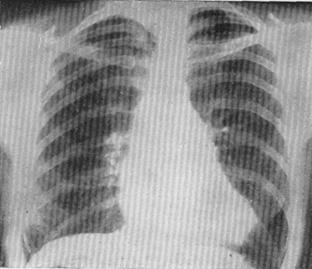

Рентгеновское исследование констатирует изменение размеров сердца за счет увеличения левого предсердия и правого желудочка. Все четыре дуги на левом контуре дифференцируются отчетливо. Однако исчезает талия сердца за счет выбухания второй (лёгочная артерия) и третьей (левое предсердие) дуг по левому контуру, а также гипертрофии и дилатации правого желудочка. Это характерно для "митральной" конфигурации сердечного силуэта (рис. 96,97).

Рис. 96,97. Рентгенограмма больного с митральным стенозом. А- прямая проекция. Усиленный легочной рисунок. Значительное увеличение дуги легочной артерии; Б- I косая проекция (правая). Контрастированный пищевод отклоняется по дуге малого радиуса (менее 7 см).

Наиболее отчётливые рентгенологические признаки увеличения левого предсердия определяются в первой косой проекции с контрастированным пищеводом. При этом пищевод отклоняется вправо и кзади. Считается, что отклонение контрастированного пищевода по дуге малого радиуса (до 6 см) характерно для митрального стеноза, а по дуге большого радиуса (свыше 6-7 см) - для митральной недостаточности. В боковой проекции отмечается увеличение правого желудочка и выбухание лёгочного ствола. Электрокардиография является ценным методом диагностики митрального стеноза. При этом обнаруживается гипертрофия левого предсердия и правого желудочка. Также диагностируются возможные нарушения сердечного ритма: мерцательная аритмия и различного рода блокады. Фонокардиография (ФКГ) также имеет большое диагностическое значение. ФКГ представляет собой объективную графическую запись сердечных тонов и шумов, выслушиваемых врачом. Регистрируется усиление интенсивности первого тона, появление третьего тона и диастолического шума с пресистолическим усилением. Второй тон чаще усилен и расщеплён (рис. 95). Эхокардиография стала вехой в совершенствовании диагностики пороков сердца. Исследования с помощью современной ультразвуковой аппаратуры по существу решают почти все диагностические проблемы при ППС. При этом выявляются размеры камер сердца, степень их гипертрофии и дилатации. Для митрального стеноза характерно увеличение размеров левого предсердия и гипертрофия правого желудочка. Также определяется диаметр атриовентрикулярного отверстия, состояние створок клапана и подклапанных структур. Определяется степень возможного кальциноза створок и фиброзного кольца. Выявляется уровень регургитации при сопутствующей митральной недостаточности. Возможно обнаружение тромбоза ушка левого предсердия.